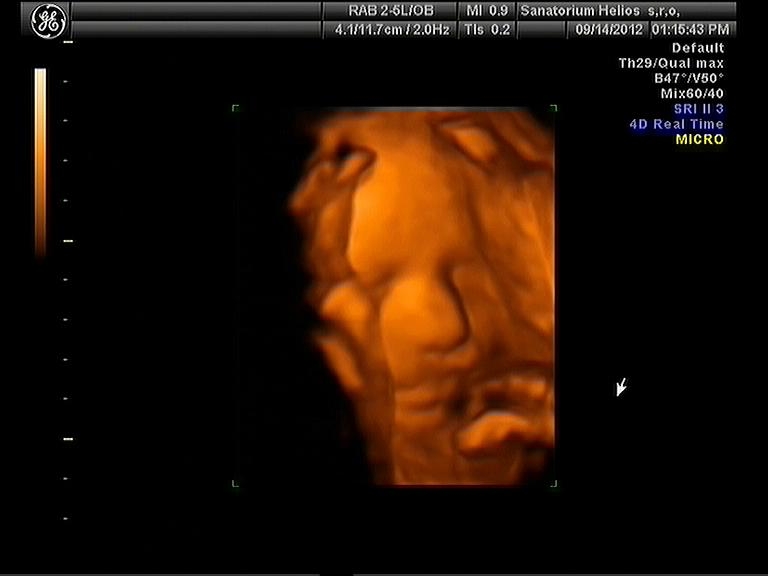

3D ultrazvuk 30. týden (Amálka je velká gymnastka :) má nožku až na čele, ručičku u brady)